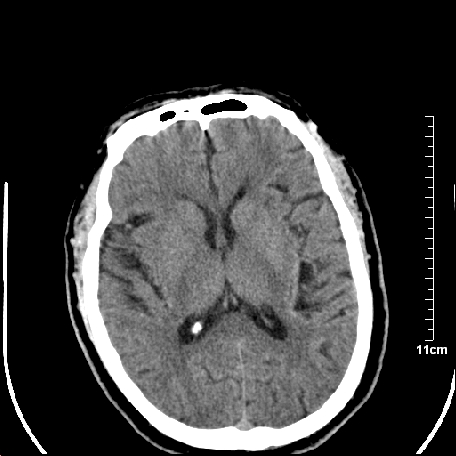

双侧外侧裂,左侧脑沟见高密度结节影,边清,还有鞍上池层面密度也高

脑血管硬化?高血红蛋白症?

高血红蛋白症可能

高血红蛋白症

高血红蛋白血征

基底动脉硬化迂曲。高血红蛋白血症。